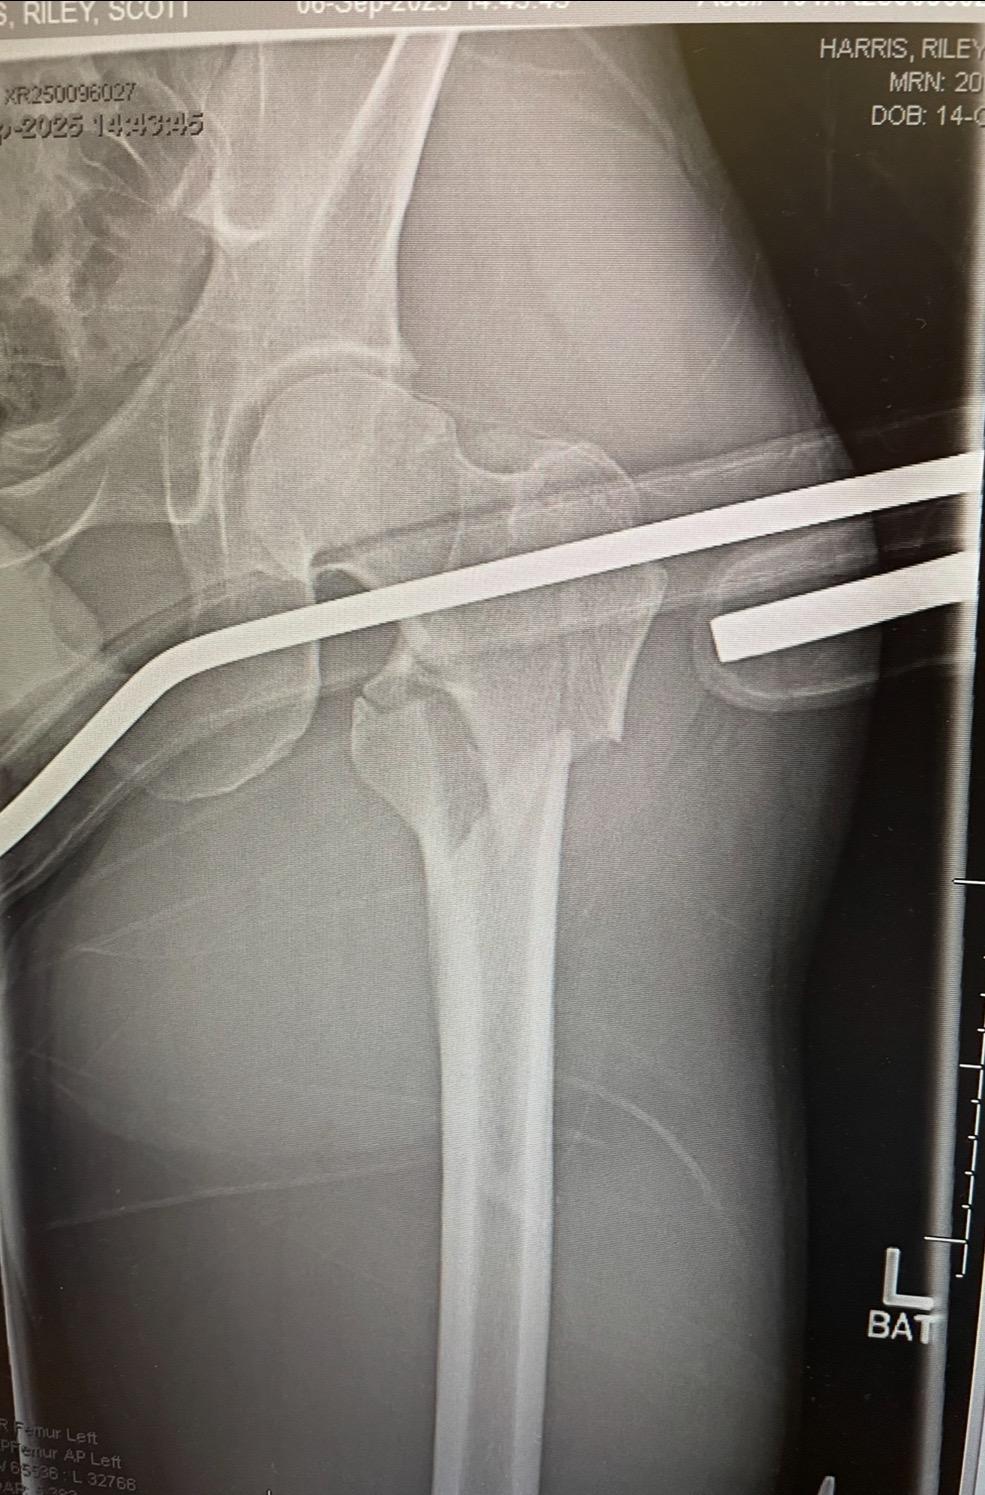

My name is Riley and on September 8, 2025, I suffered a significant injury—a fracture to my left femur—that has altered my life. On that morning while completing an errand near my home, a freak bail on my skateboard left my leg in dear condition. This injury requires extensive medical rehabilitation and a recovery period of 3 to 6 months, during which completing work is extremely difficult if at all possible. As a result, I am facing strenuous financial challenges without my regular ability to generate income, most notably my expenses for housing, food, and other necessary bills and debt payments.